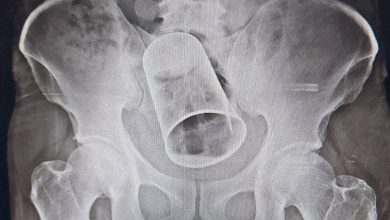

മദ്യലഹരിയില്‍ സുഹൃത്തുക്കളുടെ പരാക്രമം; യുവാവിന്റെ ശരീരത്തില്‍ കുടുങ്ങിയ സ്റ്റീല്‍ ഗ്ലാസ് ശസ്ത്രക്രിയയിലൂടെ പുറത്തെടുത്തത് പത്താംനാള്‍

ഭുവനേശ്വര്‍: സുഹുത്തുക്കള്‍ മദ്യലഹരിയില്‍ നടത്തിയ പരാക്രമത്തില്‍ യുവാവിന്റെ ശരീരത്തില്‍ കുടുങ്ങിയ സ്റ്റീല്‍ ഗ്ലാസ് പത്തുദിവസത്തിനുശേഷം പുറത്തെടുത്തു. ഗഞ്ചാം സ്വദേശി കൃഷ്ണ റൗട്ടി(45)ന്റെ ശരീരത്തിനുള്ളില്‍നിന്നാണ് ഗ്ലാസ് പുറത്തെടുത്തത്. പത്തുദിവസം മുമ്പ് ഗുജറാത്തിലെ സൂറത്തില്‍വെച്ചാണ് കൃഷ്ണ റൗട്ടിന് നേരേ അതിക്രമമുണ്ടായത്. സൂറത്തില്‍ ജോലിചെയ്യുന്ന യുവാവ് സംഭവദിവസം സുഹൃത്തുക്കള്‍ക്കൊപ്പം മദ്യപിച്ചിരുന്നു. തുടര്‍ന്ന് മദ്യലഹരിയില്‍ ഒപ്പമുണ്ടായിരുന്ന സുഹൃത്തുക്കള്‍ യുവാവിന്റെ സ്വകാര്യഭാഗത്തിലൂടെ സ്റ്റീല്‍ ഗ്ലാസ് കുത്തിക്കയറ്റുകയായിരുന്നു. പിറ്റേദിവസം മുതല്‍ യുവാവിന് കഠിനമായ വയറുവേദന അനുഭവപ്പെടാന്‍ തുടങ്ങി. പക്ഷേ, ആരോടും ഇക്കാര്യം വെളിപ്പെടുത്തിയില്ല. ഒടുവില്‍ വേദന അസഹനീയമായതോടെ യുവാവ് നാട്ടിലേക്ക് തിരിച്ചു. ഒഡീഷയിലെ ഗ്രാമത്തില്‍ എത്തിയതിന് പിന്നാലെ യുവാവിന്റെ വയറുവീര്‍ക്കാന്‍ തുടങ്ങി. മലവിസര്‍ജനവും തടസപ്പെട്ടു. ഇതോടെ ആശുപത്രിയില്‍ പോകാന്‍ ബന്ധുക്കള്‍ യുവാവിനോട് നിര്‍ദേശിച്ചു. തുടര്‍ന്ന് ഒഡീഷയിലെ ബെര്‍ഹാംപുര്‍ എം.കെ.സി.ജി. മെഡിക്കല്‍ കോളേജ് ആശുപത്രിയില്‍ ഇയാളെത്തുകയായിരുന്നു. യുവാവിന്റെ ശരീരത്തിനുള്ളില്‍ സ്റ്റീല്‍ ഗ്ലാസ് കുടുങ്ങികിടക്കുന്നത് എക്സറേ പരിശോധനയില്‍ ഡോക്ടര്‍മാര്‍ കണ്ടെത്തി. തുടര്‍ന്ന് മലദ്വാരത്തിലൂടെ ഗ്ലാസ് പുറത്തെടുക്കാന്‍ ശ്രമിച്ചെങ്കിലും ഫലംകണ്ടില്ല. ഇതോടെയാണ് യുവാവിനെ ശസ്ത്രക്രിയയ്ക്ക്…